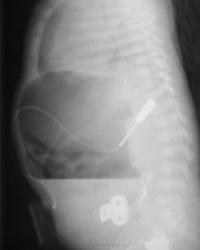

Снимки при поступлении. Клиника кишечной непроходимости. Что делали раньше из направления непонятно. Ваше мнение?

Газовый пузырь один. Второго в 12 п кишке не видно. Следы бария, не пойму где, вроде не в желудке. Может пилостеноз. Что за трубочки, не знаю.

С атрезией погорячилась, газ-то дальше есть в кишке. Признаков инвагинации не вижу. Барий в 12-п.к в тазу? На боковом снимке по задней стенке желудка непонятная плоская площадка, никогда такого не видела. Очень интересно узнать, что же это такое.

Только сейчас заметила: "клиника инвагинации"! Неужели неудачная попытка распраить?! Это растянутая подвздошная кишка?

На момент производства рентгенограмм - картина перфорации кишечника, газ и жидкость в свободной  брюшной полости. Ребенок немедленно взят в операционную, на операции инвагинация тонкой кишки в толстую, вовремя нераспознанная, с некрозом, разрывом кишечника, каловым перитонитом. Спасти ребенка не удалось...

Здравствуйте. Если чесно, мне самому не все ясно в данном наблюдении, но что имеем, то имеем.  Контрастное вещество - вероятно не барий а йодлипол, куда и зачем он был введен на предыдущих этапах исследования не совсем понятно. Катетер, судя по снимкам - в брюшной полости. Остальные подробности уже не вспомнить - около 20 лет назад...